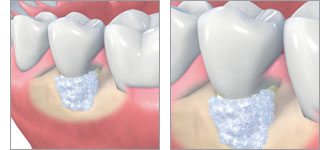

Bei größeren Defekten wird die Anlage von neuem Knochen mit einer gesteuerten Geweberegeneration (GTR - Guided Tissue Regeneration) und der Applikation regenerativer Materialien gefördert. Ziel ist, im Rahmen einer systematischen Parodontalbehandlung verloren gegangene Zahnhaltegewebe wiederaufzubauen. Es werden die Strukturen des Zahnhalteapparates ersetzt bzw. ihre Regeneration unterstützt.

Verlorenes Knochengewebe kann mit Eigenknochen aufgebaut werden. Es besteht zudem die Möglichkeit, die Bildung des Knochengewebes/Knochenaufbau mit körperfremdem Knochenersatzmaterial anzuregen (Augmentation). Hierzu wird der Eigenknochen oder das Knochenersatzmaterial während einem chirurgischen Eingriff in die Knochentasche eingefüllt. Im Laufe der Zeit wird das Material durch den Körper abgebaut und durch körpereigenen Knochen ersetzt (Parodontaltherapien).

Wichtig ist, das Einwachsen eines langen Saumepithels zu verhindern, da dieses den Zahn bindegewebsartig umschließt und es dadurch zu keiner festen Verankerung im Kieferknochen kommen kann. Da die Epithelzellen sehr schnell von der Zahnkrone aus in Richtung der Zahnwurzel wachsen, muss diese Zellen der Weg versperrt werden.

Die effektivste Möglichkeit ist, die Wurzeloberfläche mit einer Membran abzudecken. Diese Membran verhindert das Einwachsen der Epithelzellen „von oben“. Die langsamer wachsenden Gewebe des Zahnhalteapparates bauen sich unter der Membran auf. Man unterscheidet zwischen resorbierbaren, sich nach einer festgelegten Zeit auflösenden Membranen und nicht resorbierbaren Membranen, die nach einem festgelegten Zeitraum chirurgisch entfernt werden müssen.